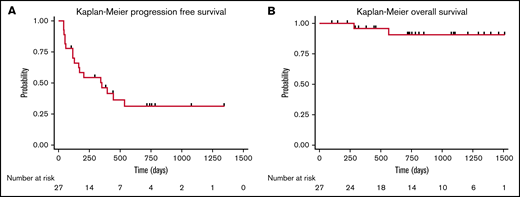

Lymphodepletion was administered to all patients treated with CD30.CAR-T cells. Bendamustine was the lymphodepletion regimen for the first 8 patients treated (30%), and a combination of bendamustine and fludarabine was used for the remaining 19 patients of the cohort (70%). Five patients (19%) were treated with CD30.CAR-T cells at a dose of 1 × 108 cells/m2 as part of dose escalation. The remaining 22 patients (81%) were treated at a dose of 2 × 108 cells/m2. Following lymphodepletion and CD30.CAR-T cells, the ORR at 6 weeks was 71% with 18 patients (67%) achieving a CR. Two patients had stable disease (SD) and subsequently progressed, and 6 patients (22%) had progressive disease (PD). Overall, 17 patients (63%) in this cohort developed progression with a median PFS of 352 days (95% confidence interval [CI]: 116-not reached), and 2 patients died (7%) with a median OS of not reached (Figure 2).

Cohort survival. PFS (A) and OS (B) for all patients treated with CD30.CAR-T cell therapy.

Cohort survival. PFS (A) and OS (B) for all patients treated with CD30.CAR-T cell therapy.